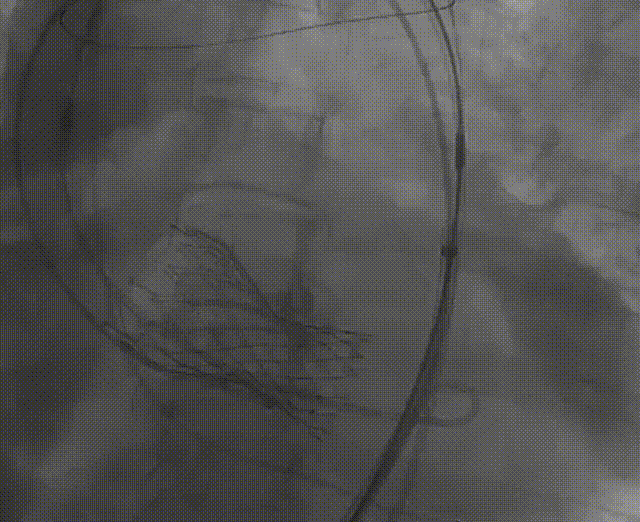

综合考虑瓣环直径、左室流出道直径、钙化分布等因素,彭小平主任团队顺利为患者植入一枚VenusA-Valve®L26型号的人工主动脉瓣膜,借助Snare,克服了超大横位心等难题,血流动力学效果非常好。

Snare辅助跨瓣

VenusA-Valve®完成释放

术前跨瓣差压93mmHG

术后跨瓣压差2mmHG